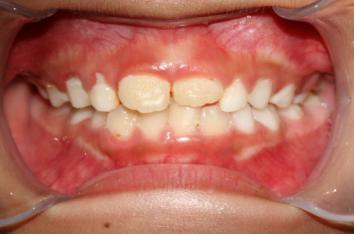

❸ 牙齿不齐:影响咬合关系,影响美观。

前

后